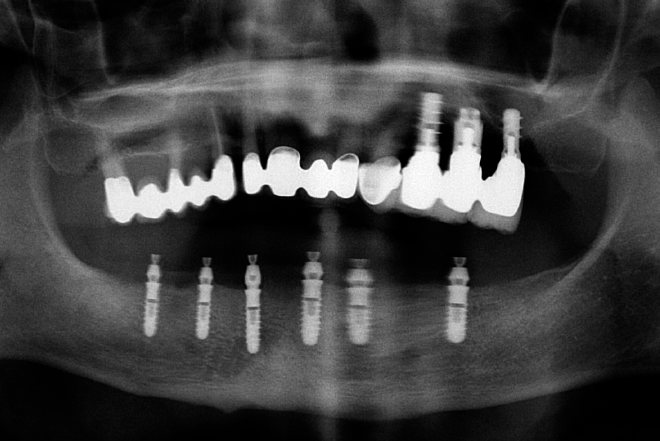

L’esigenza del paziente era quella di riabilitare in una sola seduta l’arcata inferiore edentula tramite protesi fissa a supporto implantare. Il moderato grado di atrofia, associato ad un discreto mantenimento dei normali rapporti intermascellari sul piano frontale, verticale ed antero-posteriore, avevano indirizzato la scelta verso una riabilitazione implanto-protesica tipo Toronto Bridge. Questo tipo di protesi permette la sostituzione protesica dei tessuti molli per evitare denti troppo lunghi e inoltre la disposizione implantare non deve necessariamente corrispondere con l’emergenza degli elementi dentali. L’esame radiologico ortopanoramico (Fig. 1) e l’esame Cone Beam effettuato a distanza di alcuni mesi dalle estrazioni (Figg. 2, 3) evidenziavano una sufficiente conservazione della cresta ossea in senso verticale e degli spessori ossei vestibolo-orali per l’inserimento di 6 impianti 4,1 x 12 mm.

L’esame radiologico ortopanoramico effettuato subito dopo l’intervento ha confermato il corretto posizionamento degli impianti e dei monconi (Fig. 32).